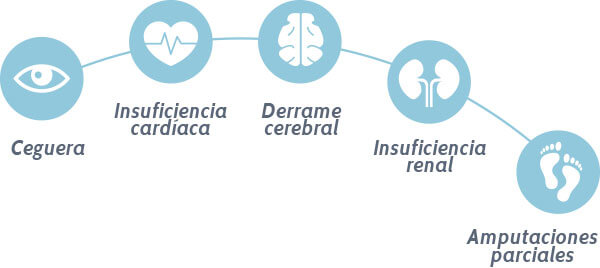

Y ya tienen una complicación adicional como lo son deterioro renal, deterioro de la visión, deterioro de los nervios o amputación de algún miembro.

Y es tan fácil, natural y efectivo este sistema que quienes lo aplican olvidan las complicaciones más terribles de esta enfermedad…

Hoy todos ellos viven felices y borraron de sus vidas el miedo permanente de una amputación.

En recientes inicios de mi carrera como investigador, llegaban un sin número de páncreas, hígados, córneas y piernas amputadas al centro de investigaciones para su estudio.

Detrás de todos estos órganos sumergidos en formol, se encontraban familias destrozadas que habían perdido a sus abuelos, esposas, padres e inclusos hijos.

Indagando fue que conocí a cirujanos, oftalmólogos y ortopedistas encargados de recoger las muestras de pacientes fallecidos a causa de la diabetes.

Hablé con cada uno de ellos y quedé en shock cuando me dijeron que habían incluso familiares con diabetes complicada entre el grupo de médicos y que estaban asombrados de la cantidad de personas a nivel mundial que estaban perdiendo la batalla en contra de la diabetes.

✓ Libre del miedo de una ceguera, una amputación o un coma diabético;

La neuropatía, la retinopatía, las amputaciones serán cosa del pasado;